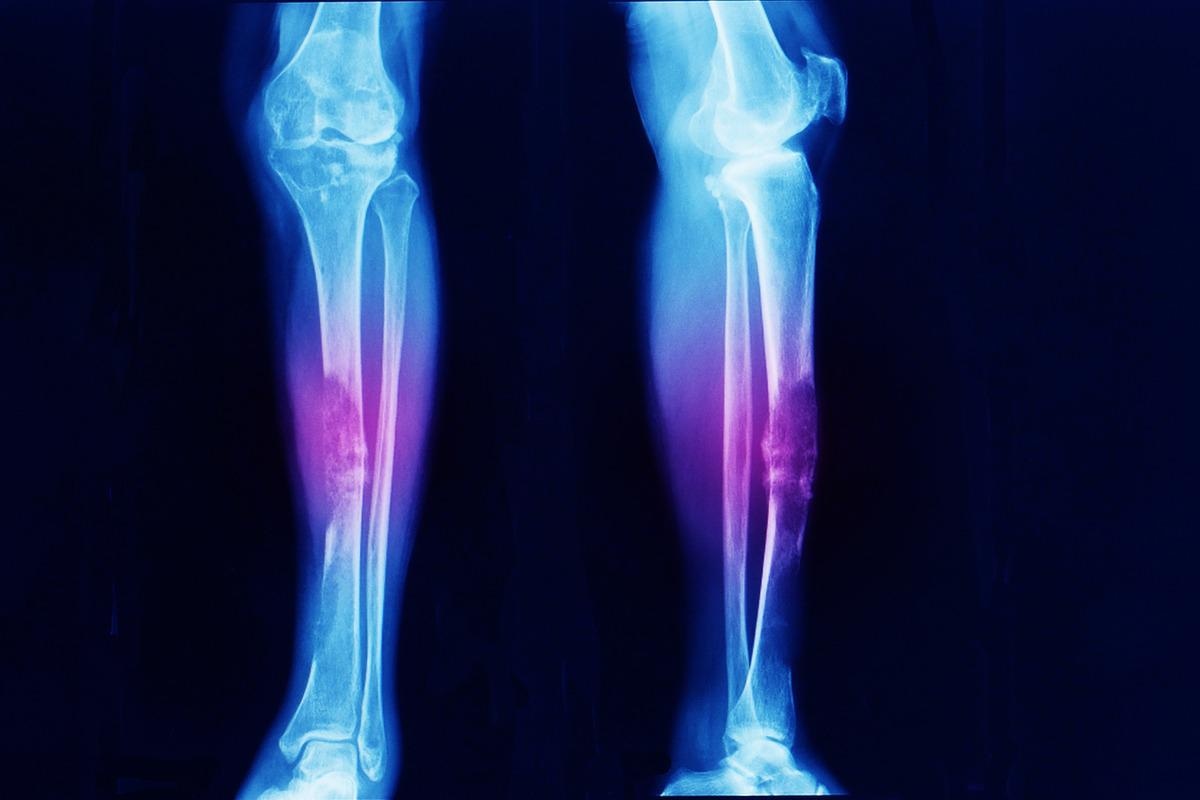

Image Credit: Darya Komarova/ShutterstockImage Credit: Darya Komarova/Shutterstock

Local discomfort, bone swelling, and palpable bony masses are common clinical symptoms in the first decade of life and are frequently associated with bone malformation. Clinical findings include headache and cranial nerve palsy. Enchondromas on the extremities are frequently apparent as lumps implanted inside the phalanges, metacarpal, and metatarsal bones on physical examination. Long tubular bones, such as the tibia, femur, and/or fibula, are usually afflicted by enchondromas; flat bones, particularly the pelvis, can also be impacted. The lesions can affect numerous bones and are frequently asymmetrically distributed, affecting one side of the body solely or predominately. Bones that have been affected are frequently shorter and misshapen.

Clinical and conventional radiological examinations, rather than genetic testing, are used to diagnose Ollier disease. The most effective method for diagnosing numerous lesions and malignant transformation is radionuclide bone imaging. It can aid in the diagnosis and prognosis of Ollier disease. One of the most basic instruments for diagnosing bone illnesses is an X-ray. The lesions in Ollier disease are mostly oval and develop in the shaft and metaphysis of short or long bones.